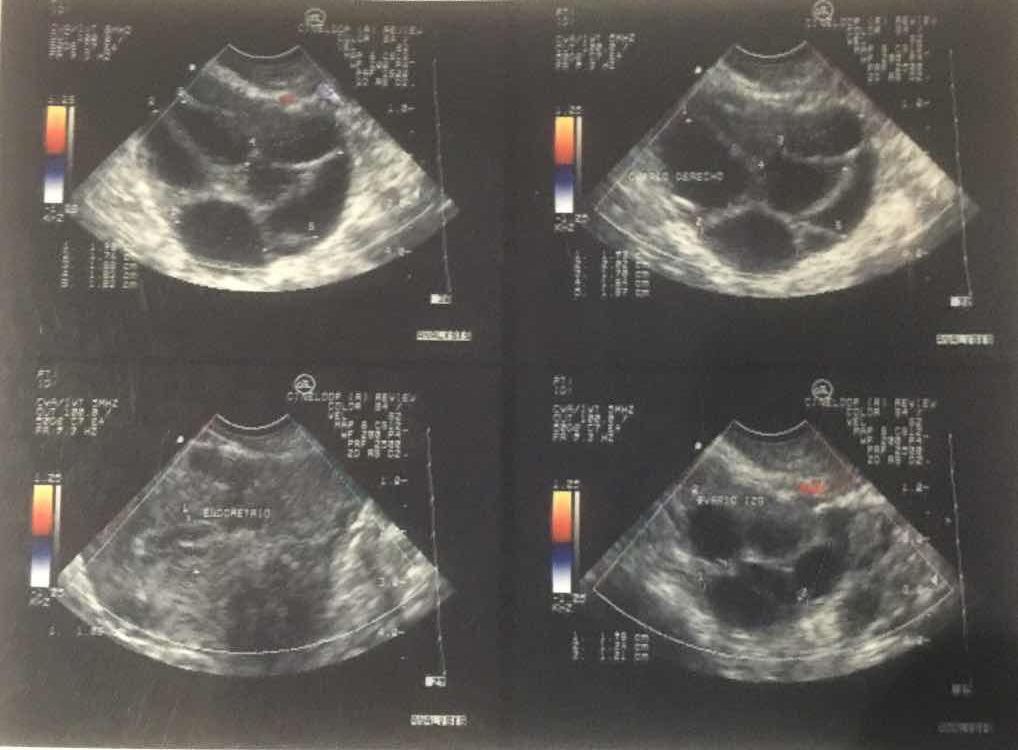

Fertilización In Vitro

FIV, es una técnica de reproducción asistida, en donde previa estimulación ovárica se realiza la captura de óvulos, los cuales, son fecundados fuera del cuerpo de la madre con los espermatozoides, dando lugar a la formación de embriones; todo esto es realizado en un laboratorio altamente equipado para este fin.